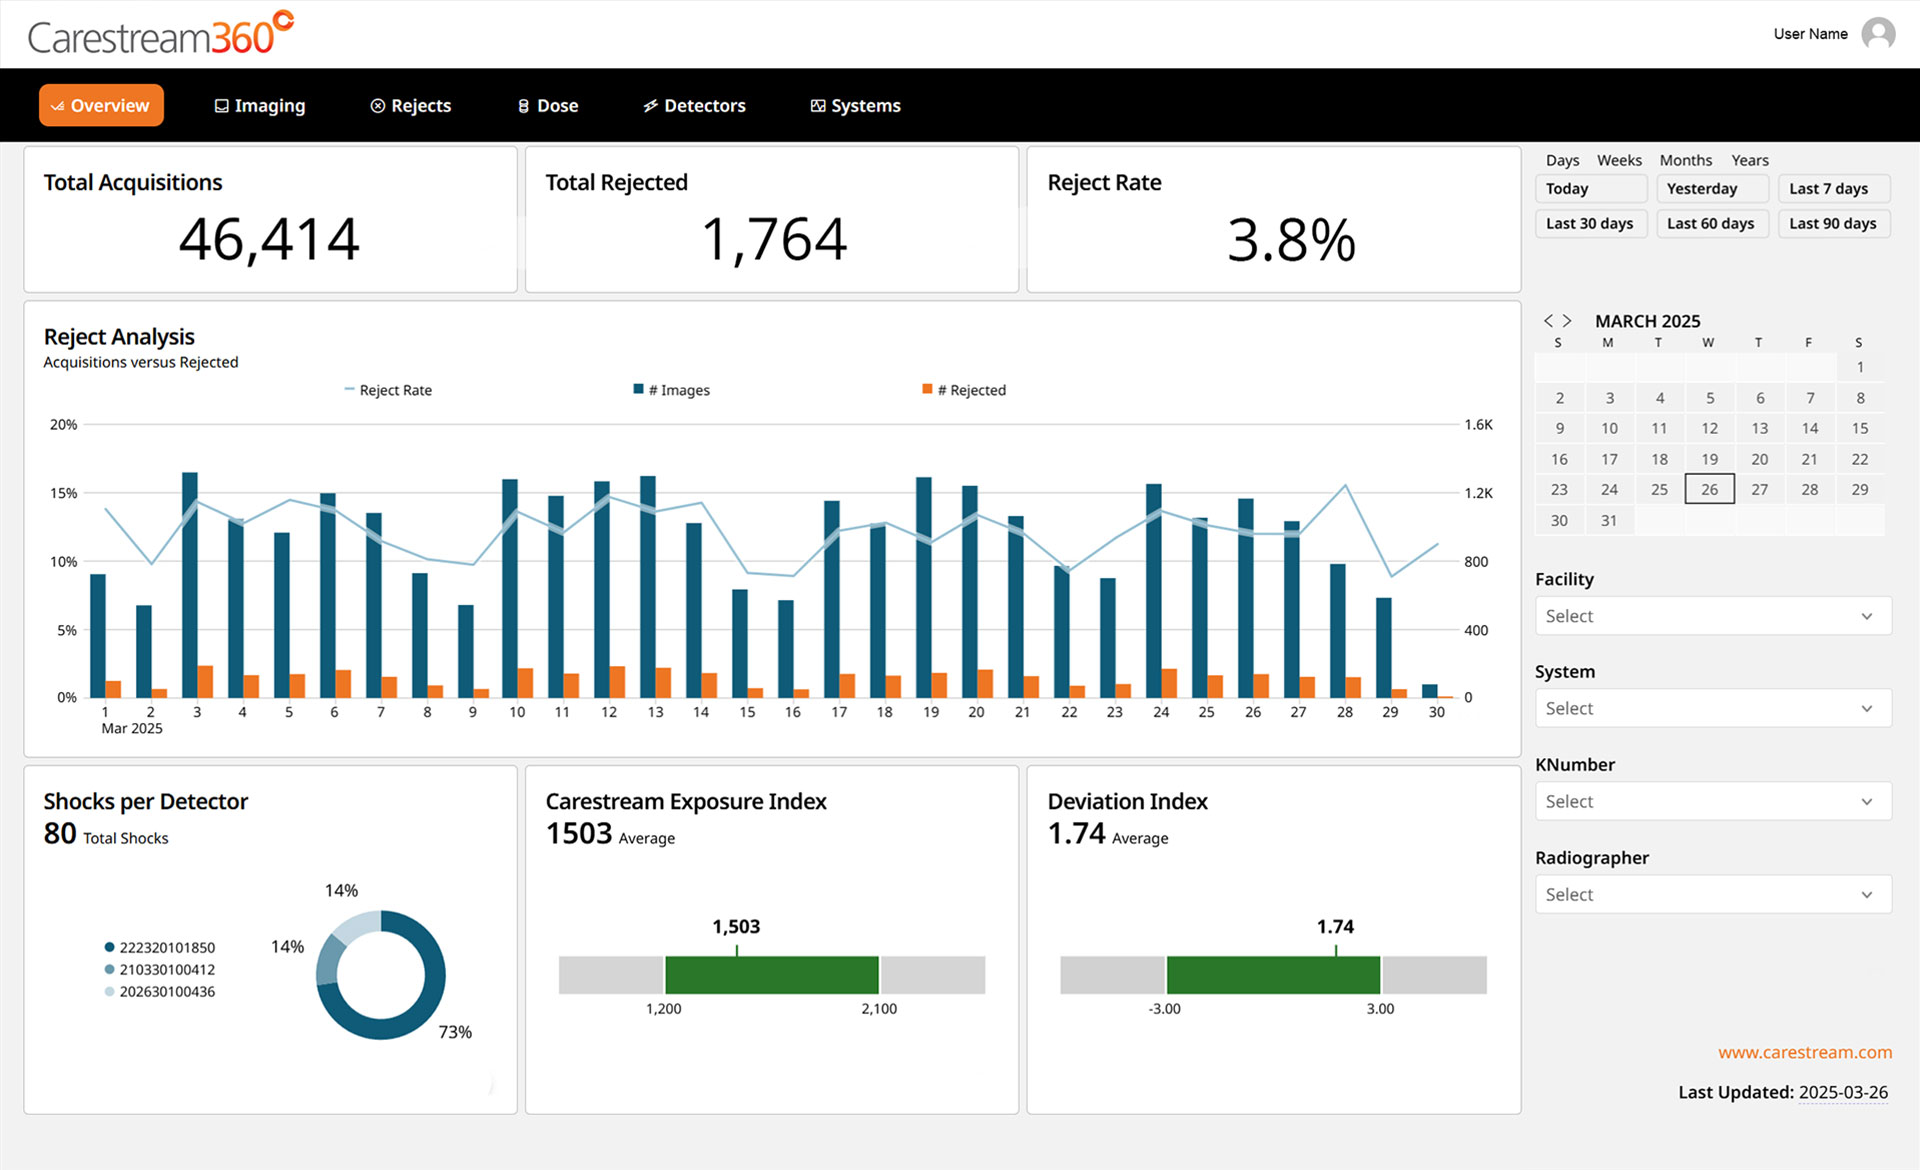

Carestream 360º is an advanced analytics dashboard designed to help radiology departments track key performance metrics, analyze imaging trends, and optimize operational efficiency. It automatically collects critical data from all connected Carestream DR systems and consolidates it into a single, intuitive dashboard, providing a comprehensive view to drive smarter decision-making.

Carestream 360º is designed with interactive tools that allow you to filter, explore, and export data effortlessly, empowering you to gain insights faster, interact intuitively, and make informed, data-driven decisions.

- Filter with Ease – Quickly refine data using intuitive, pre-set filters that allow you to focus on the metrics that matter most.

- Drill-Down Analysis – Dive deeper into trends and performance metrics to support more informed decision-making.

- Exportable Cards – Easily extract key insights for sharing, reporting, or further analysis.

Carestream 360º transforms complex performance metrics into clear, actionable insights through a series of intuitive dashboard pages. Designed for efficiency, it helps you: